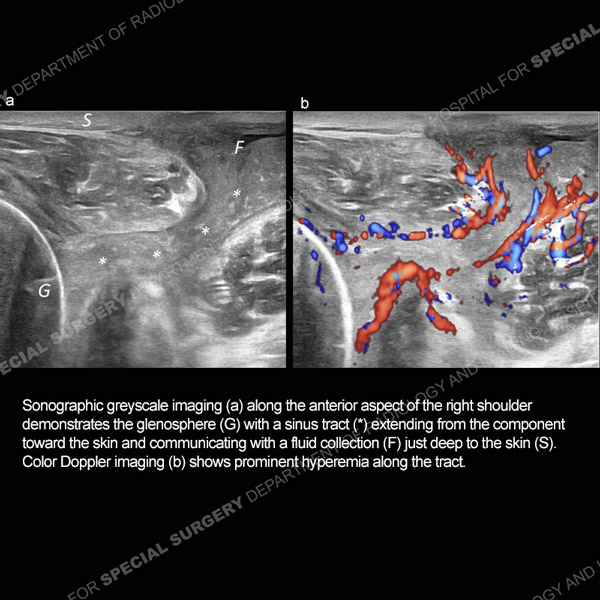

Ultrasound of the month represents a collection of interesting and sometimes diagnostically challenging cases that demonstrates the utility of ultrasound in the diagnosis and treatment of a variety of musculoskeletal conditions. The cases will be illustrative of both normal and pathologic sonographic anatomy.

Featured Ultrasound of the Month CaseCase 186: 64-year-old woman with new left ring finger soft tissue swelling. |